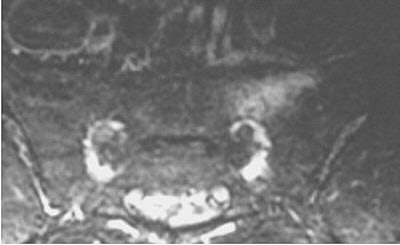

| MRI of sacrum in an ultramarathoner showing abnormal signal of a stress fracture. Image courtesy of Duke University Medical Center, Durham, NC. |

However, Major continued, "when the MR was done in one person, a sacral stress fracture was found. The others had MR also, and they too had sacral stress fractures. All along they’re thinking they have disc disease, and so it’s probably occurring much more commonly than we think. Making the diagnosis is key, and it’s a very easy diagnosis to make with MR."